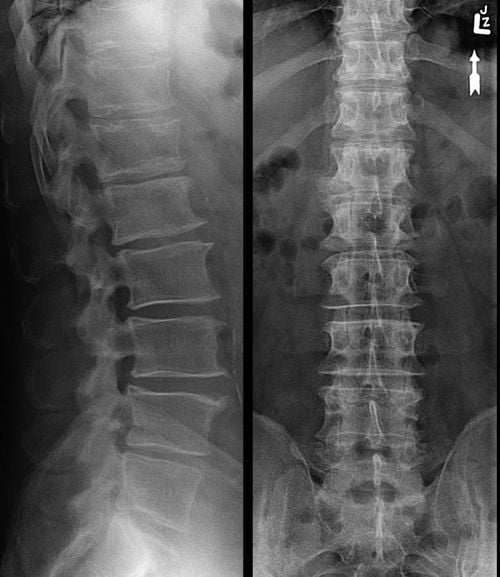

Самым информативным инструментальным исследованием становится рентгенография позвоночного столба в двух проекциях. На изображениях визуализируются подвергшиеся деструктивным изменениям диски и позвонки.